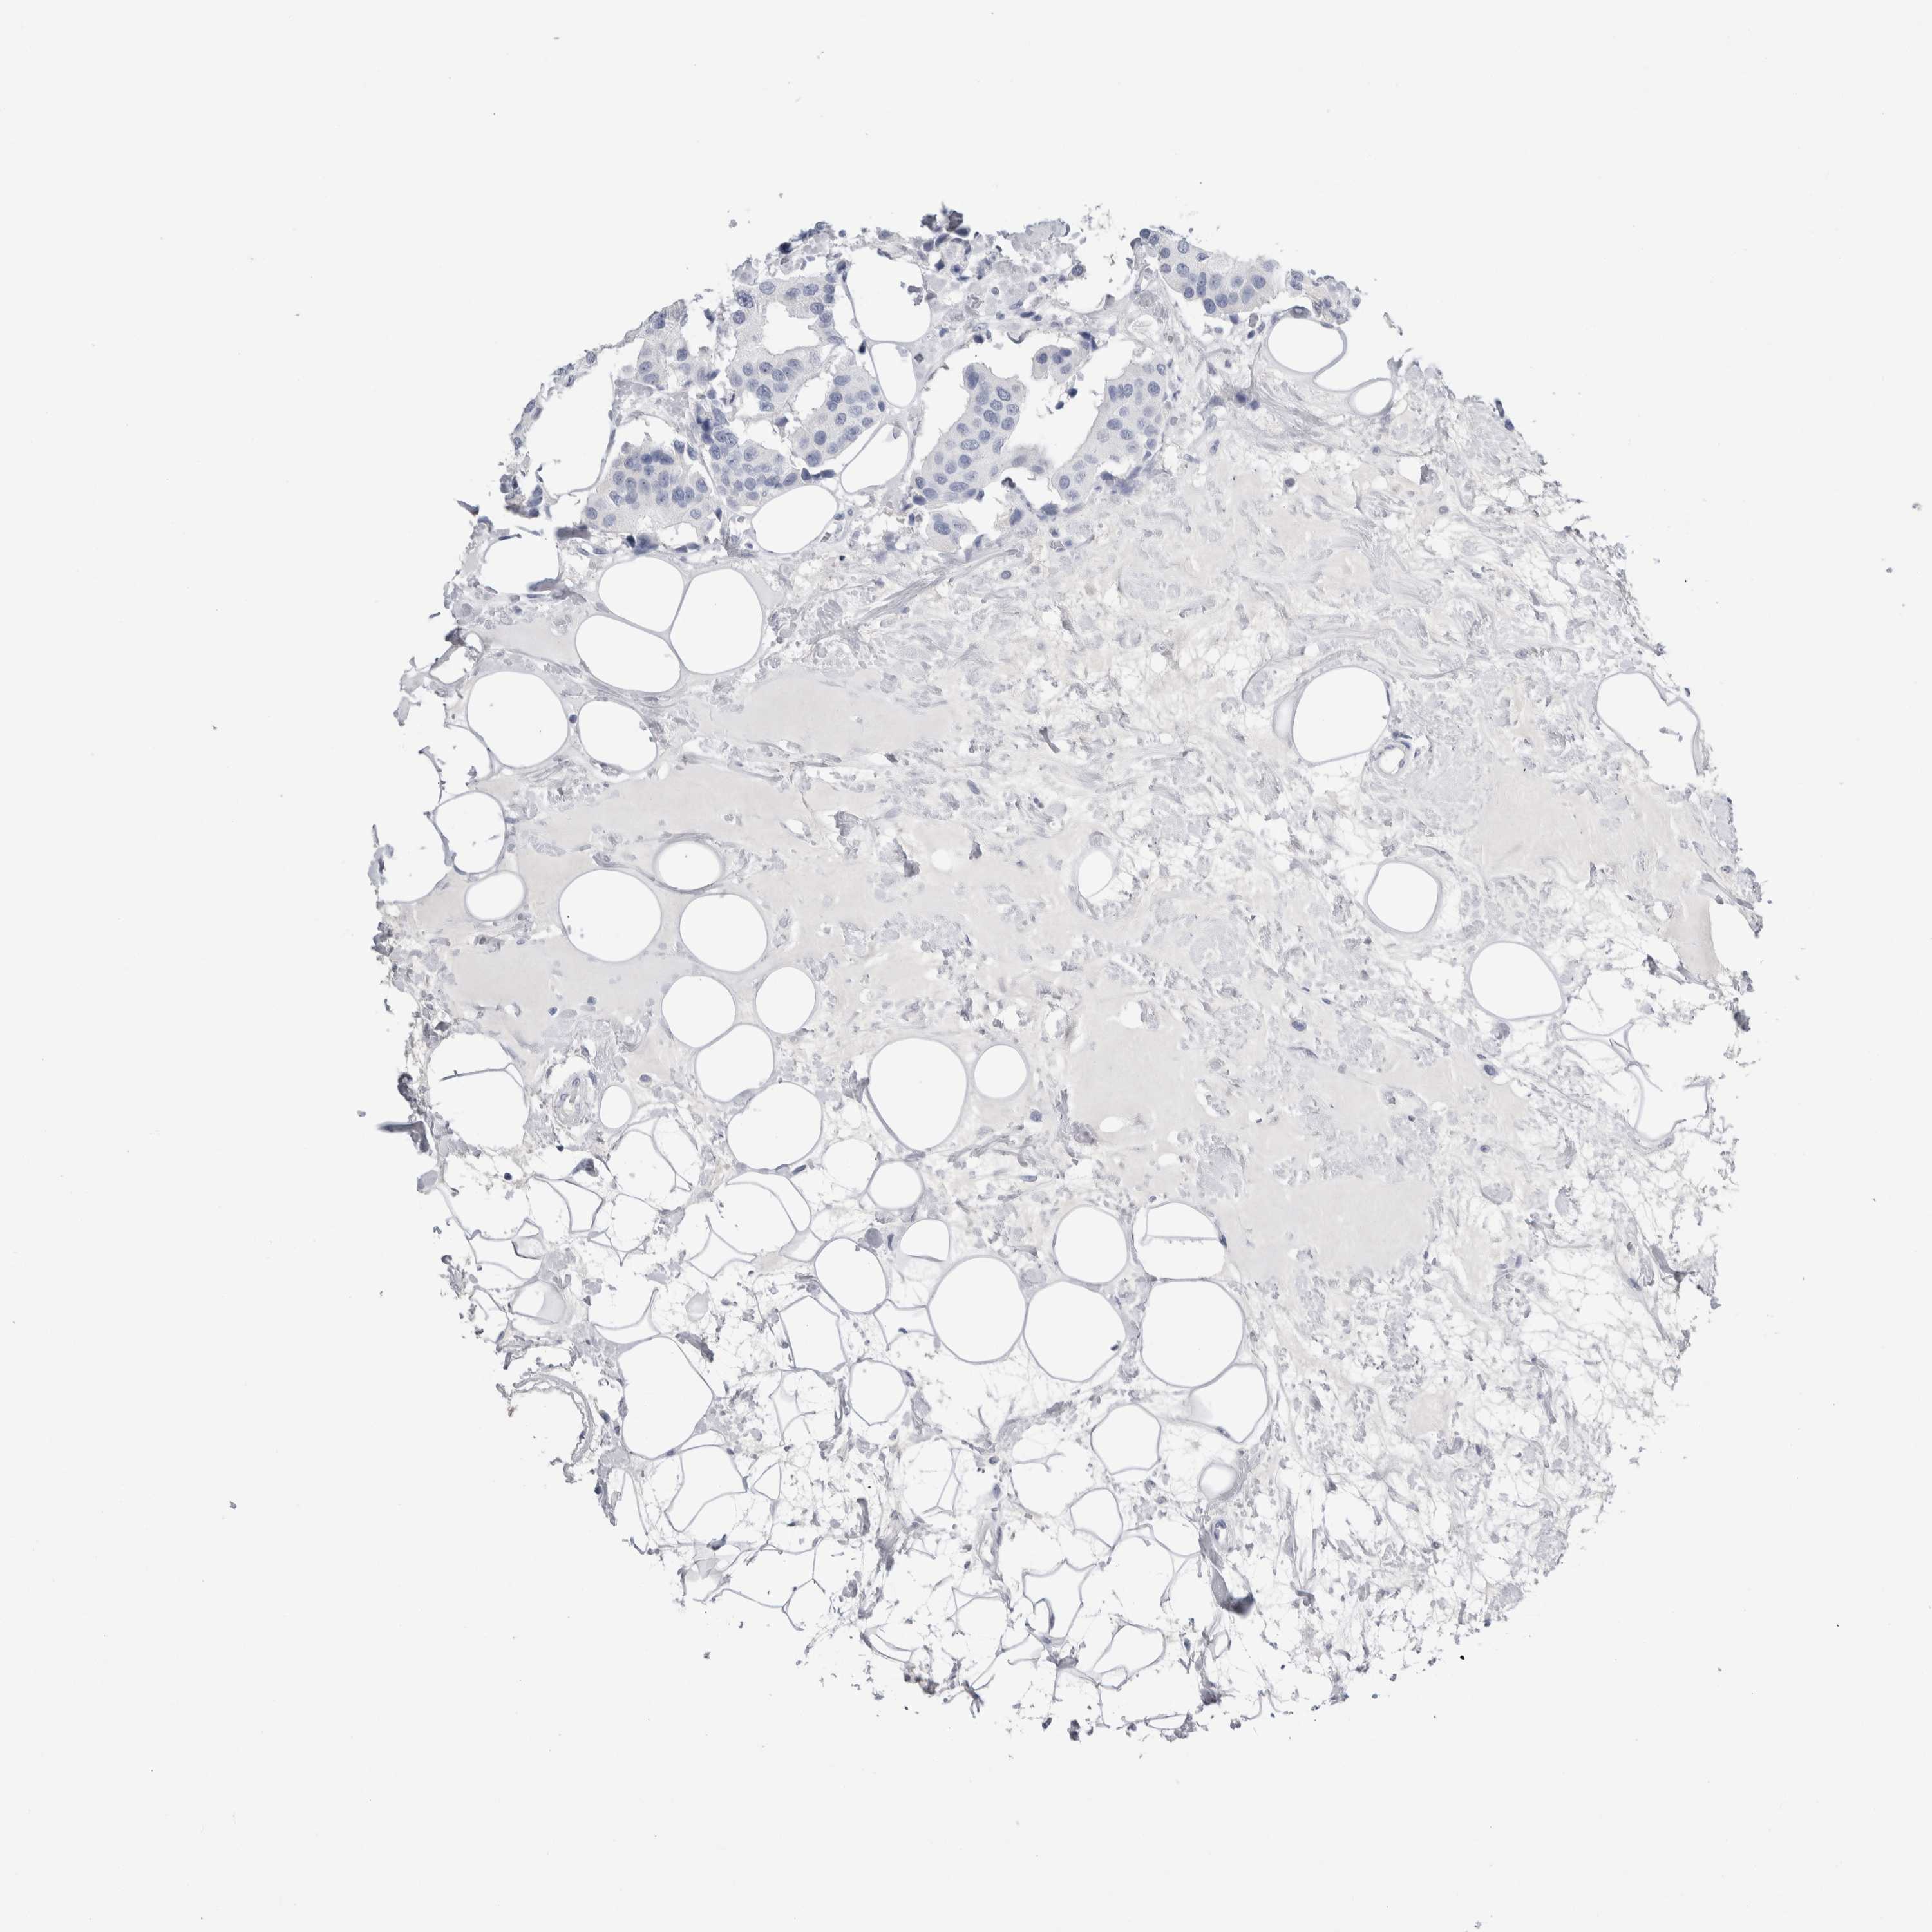

CANCER BREAST CANCER Show tissue menu

BRCA TCGA BRCA VALIDATION PROTEIN EXPRESSION